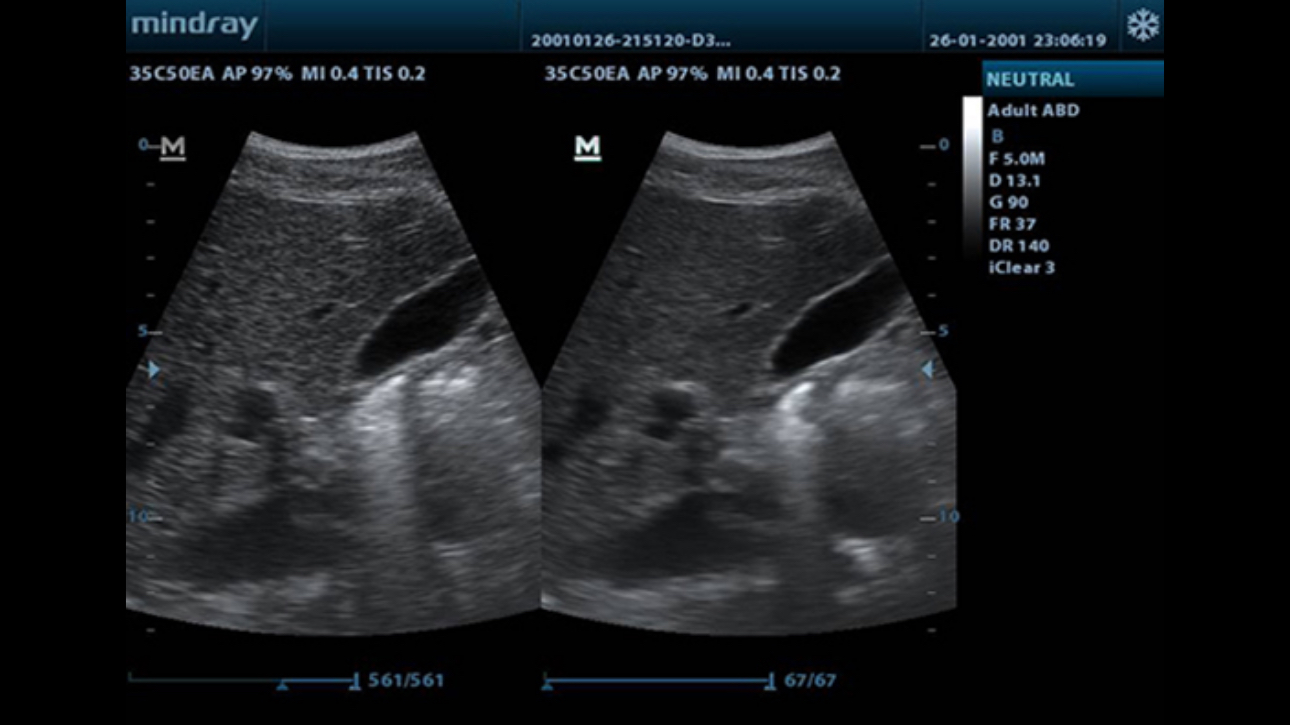

Tissue Harmonic Imaging

Utilizing second harmonics generated from tissue boundary layers, THI significantly enhances contrast resolution and improves image quality especially for technically difficult subjects.

TSI

Tissue Specific Imaging optimizes the image quality based on the properties of the tissue being scanned. Four imaging options are available including general, muscle, fluid and fat.

ExFOV

Discover better diagnostic information through extended view of the anatomical structure on all convex and linear probes.